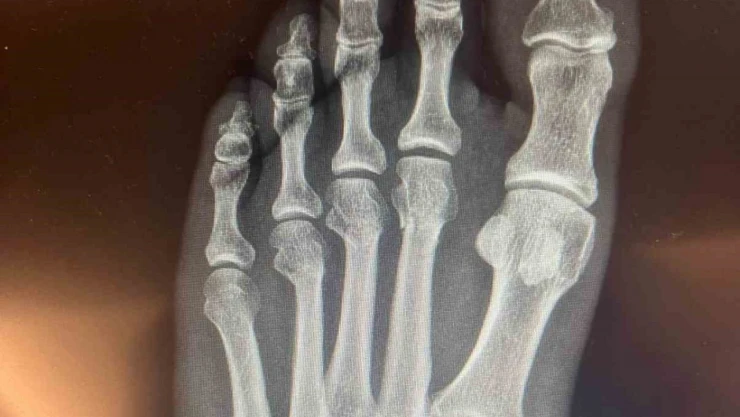

Cumhuriyet Halk Partisi (CHP) Genel Başkanı Özgür Özel, sosyal medyada yer alan 'ayağından vuruldu' iddialarına ilişkin, kırılan ayağının röntgen filmlerini paylaştı.

CHP Grup Başkanvekili Ali Mahir Başarır, geçen hafta TBMM’deki özel oturum öncesi gazetecilere yaptığı açıklamada, CHP Genel Başkanı Özgür Özel’in evde geçirdiği kaza sonucu ayağında ufak çaplı kırılma olduğunu duyurmuştu. Özel’in ayağında oluşan kırık hakkında sosyal medyada, Özel’in ‘ayağından vurulduğu’ iddiaları yer almıştı. Özel, tartışmalara ilişkin ayağının röntgen filmlerini paylaştı.